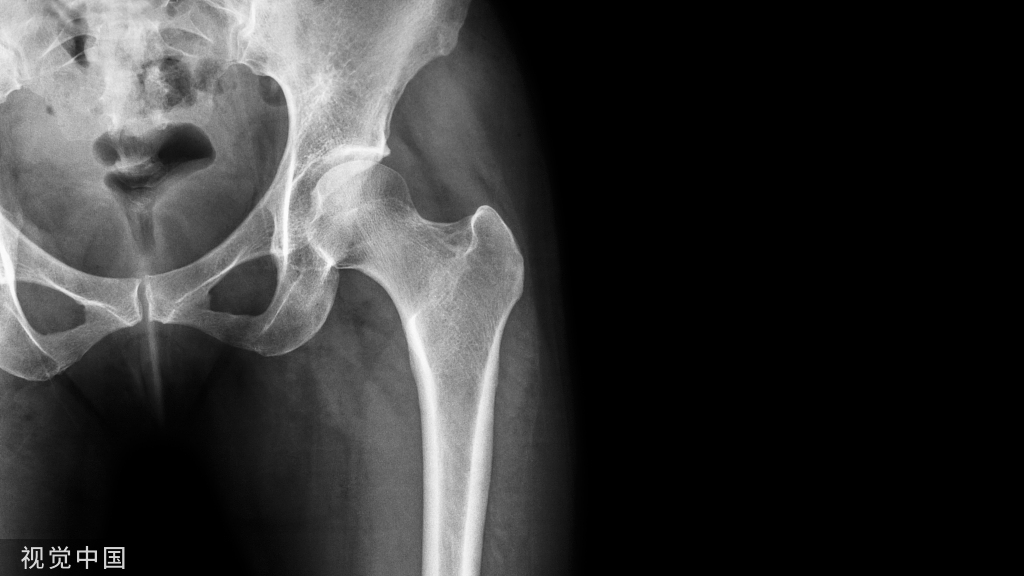

上图X光片显示髂骨大块取骨遗留的缺损。虽然保留了包括髂前上棘在内的髂骨前缘,但因缺损太大,即使穿衣时也难以遮盖畸形。从髂嵴后方切除多余骨质后难看的外形得以改善。